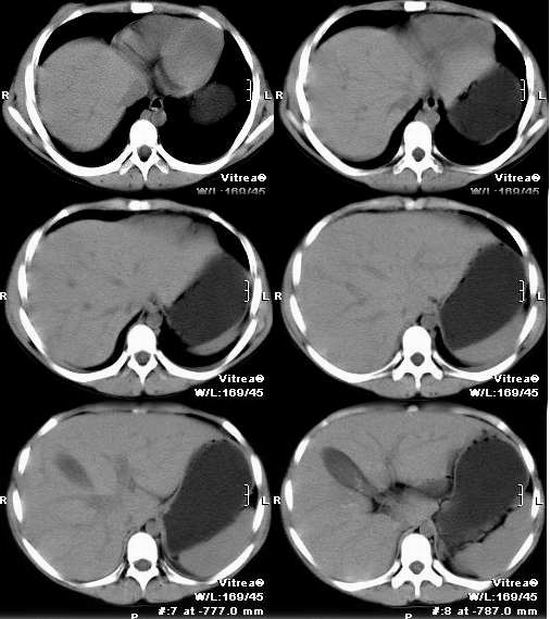

CT01086: (K) 腹部病变2(已经手术,病理结果几天后公布)

女性,14岁,腹部逐渐增大一年余,近二个月增大明显加快,在当地医院多次检查,未能确诊。无发热、 无贫血、血象正常,原食欲及饮食正常,近来食后感饱胀。月经尚未潮,第二性征不明显。 肿块高密度ct值754.5-964. ...

手术病理结果-----腹膜后畸胎瘤伴内胚窦瘤,钙化部分病理为畸胎瘤,实质肿块为内胚窦瘤。---学习了!

手术病理结果-----腹膜后畸胎瘤伴内胚窦瘤,钙化部分病理为畸胎瘤,实质肿块为内胚窦瘤

畸胎瘤及卵黄囊瘤